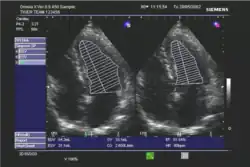

Die Ejektionsfraktion kann mit verschiedenen Untersuchungsverfahren gemessen werden, in absteigender Häufigkeit:

- Echokardiographie

In der klinischen Praxis erfolgt die Abschätzung der Ejektionsfraktion häufig nach dem visuellen Eindruck; dies wird bei subjektiv normaler Pumpfunktion als ausreichend angesehen. Bei eingeschränkter Pumpfunktion sollte eine quantitative Bestimmung mit Hilfe der Scheibchensummationsmethode nach Simpson erfolgen;[3] die Quantifizierung mittels M-Mode nach Teichholz wird als zu ungenau angesehen.[3][4]